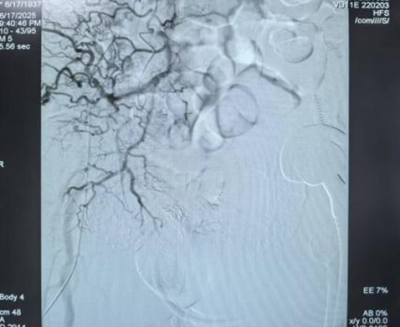

术后前列腺动脉栓塞良好